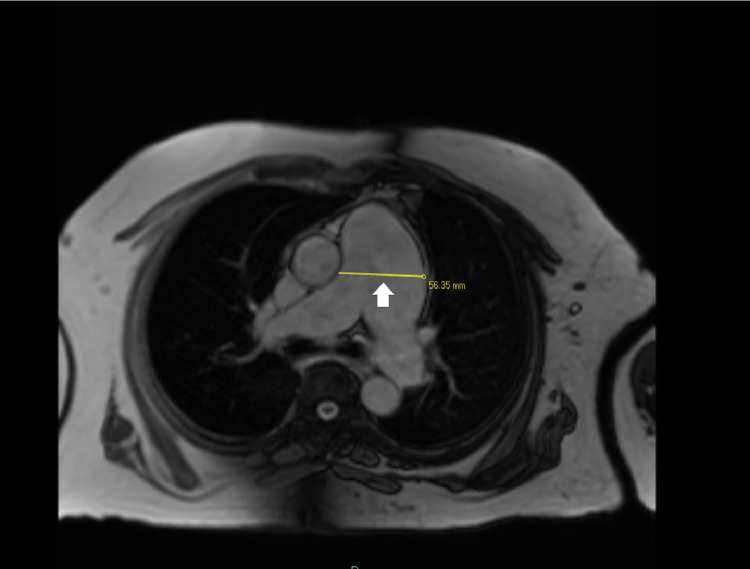

Cardiac MRI without contrast (Fig. 4) illustrated MPA aneurysm with a 5.6 cm diameter and asymmetric dilation of the left pulmonary artery (3.7 cm) compared to the right pulmonary artery (2.9 cm). It also demonstrated RVOT dilatation which can be seen in Fig. 5 and Video 1. Aneurysmal MPA was found to be in close proximity to the left main and left anterior descending coronary artery. It represented a tri-leaflet pulmonic valve with moderate leaflet thickening and mild regurgitation.

Fig. 4.

Cardiac MRI imaging for pulmonary artery aneurysm: this cardiac MRI scan specifies the diameter of pulmonary artery aneurysm as 56.35 mm (5.6 cm) with the yellow line (white arrow).